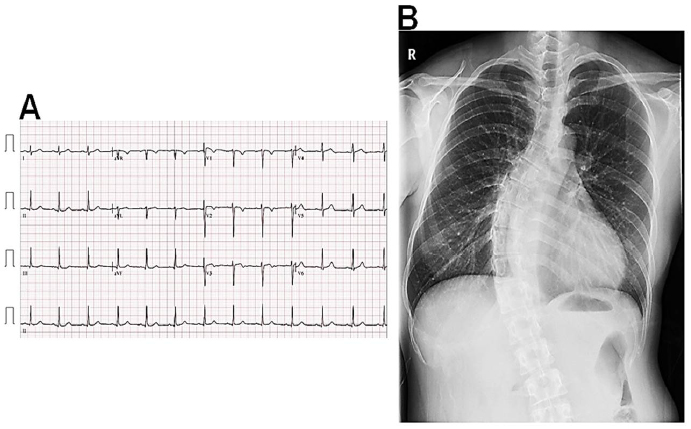

Figure 1: Electrocardiography and chest radiography at the initial admission Electrocardiography shows sinus rhythm with non-specific ST-T segment changes (A). Chest radiography shows mild cardiomegaly with tortuous thoracic spines (B).